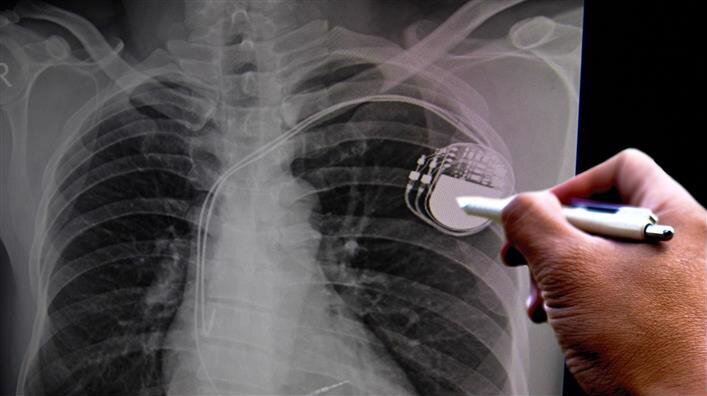

Процедура эта хорошо отработана. На Западе взрослым людям кардиостимуляторы сейчас устанавливают вообще амбулаторно, под местным обезболиванием, пациент в тот же день может идти домой. В подключичную вену вводят тоненький проводок-катетер, который идет к сердцу, на конце его электрод. Проводок закрепляют чаще всего в правом желудочке сердца, а само тело кардиостимулятора – основную его часть – имплантируют под грудную мышцу. Стимулятор практически не заметен, например, глядя на человека в бане, можно не понять, что он у него установлен.

Современные кардиостимуляторы – это миникомпьютеры, которые оценивают множество параметров, реагируют на изменение ритма, не просто навязывают определенную частоту, а дают стимул только тогда, когда это нужно для сердца.